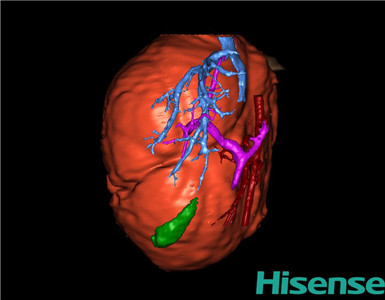

将0.625mm双源薄层CT资料的静脉期和动脉期Dicom格式文件导入海信CAS系统。

通过调节窗宽窗位调整CT序号,对肝实质,胆囊,下腔静脉,肿瘤,肝动脉、门静脉及肝静脉等进行三维重建;系统自动计算肝脏体积。

模拟手术操作,自动计算切除肝体积、肿瘤体积、剩余功能性肝体积。

肝脏体积为218.1ml,肿瘤体积为1570ml,肿瘤体积为肝脏体积的7.2倍,通过比对1-3月正常肝脏体积为174.85±58.11ml,通过术前模拟手术,精准判断切除后剩余肝脏体积能耐受,避免肝衰竭发生。

术前三维重建:

重建图片